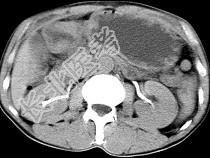

- 单项选择题男,56岁, 无规律上腹痛,左锁骨上淋巴结肿大, 消瘦、乏力,影像检查如图, 最可能诊断为 ( )

A、胃及腹腔淋巴瘤

B、胃癌并盆腔种植

C、胃溃疡穿孔

D、肠系膜淋巴管瘤

E、腹膜结核